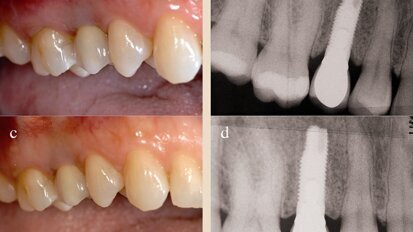

Neoss photos

Neoss Implantat System